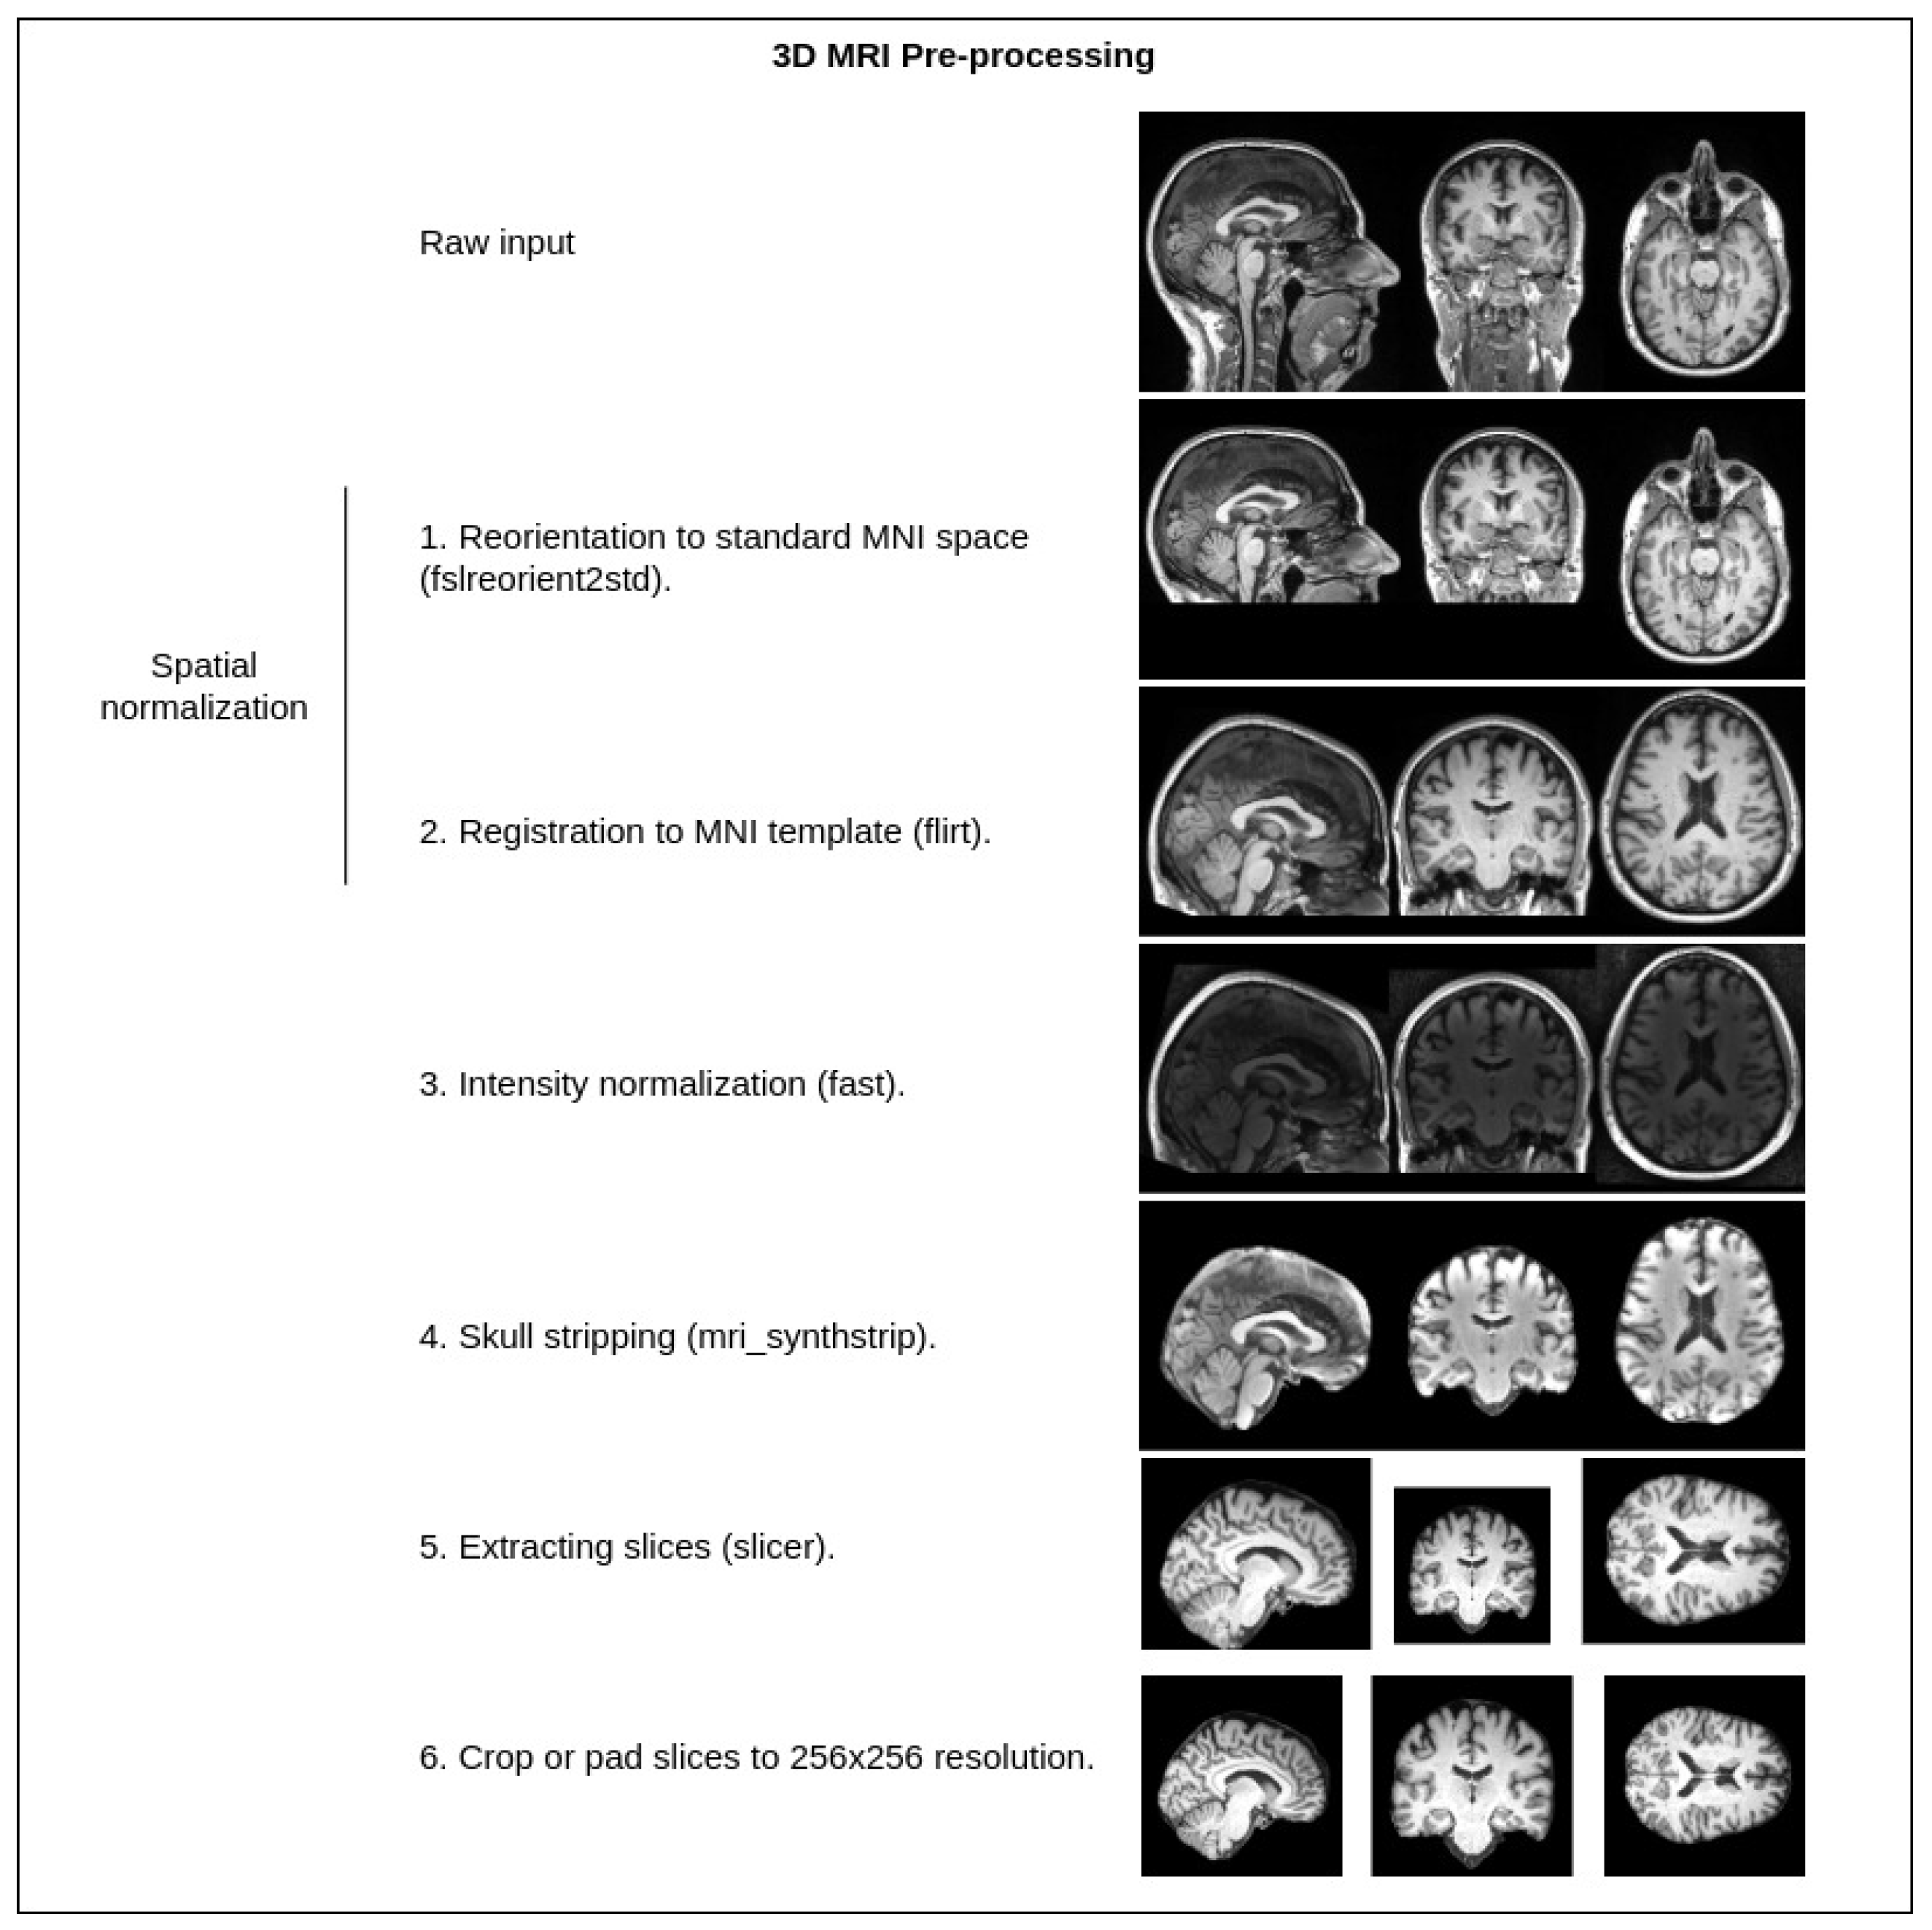

3. Materials and Methods

3.1. Upscale Network

3.1.1. Degradation

3.1.2. Loss Functions

3.2. Denoise Network